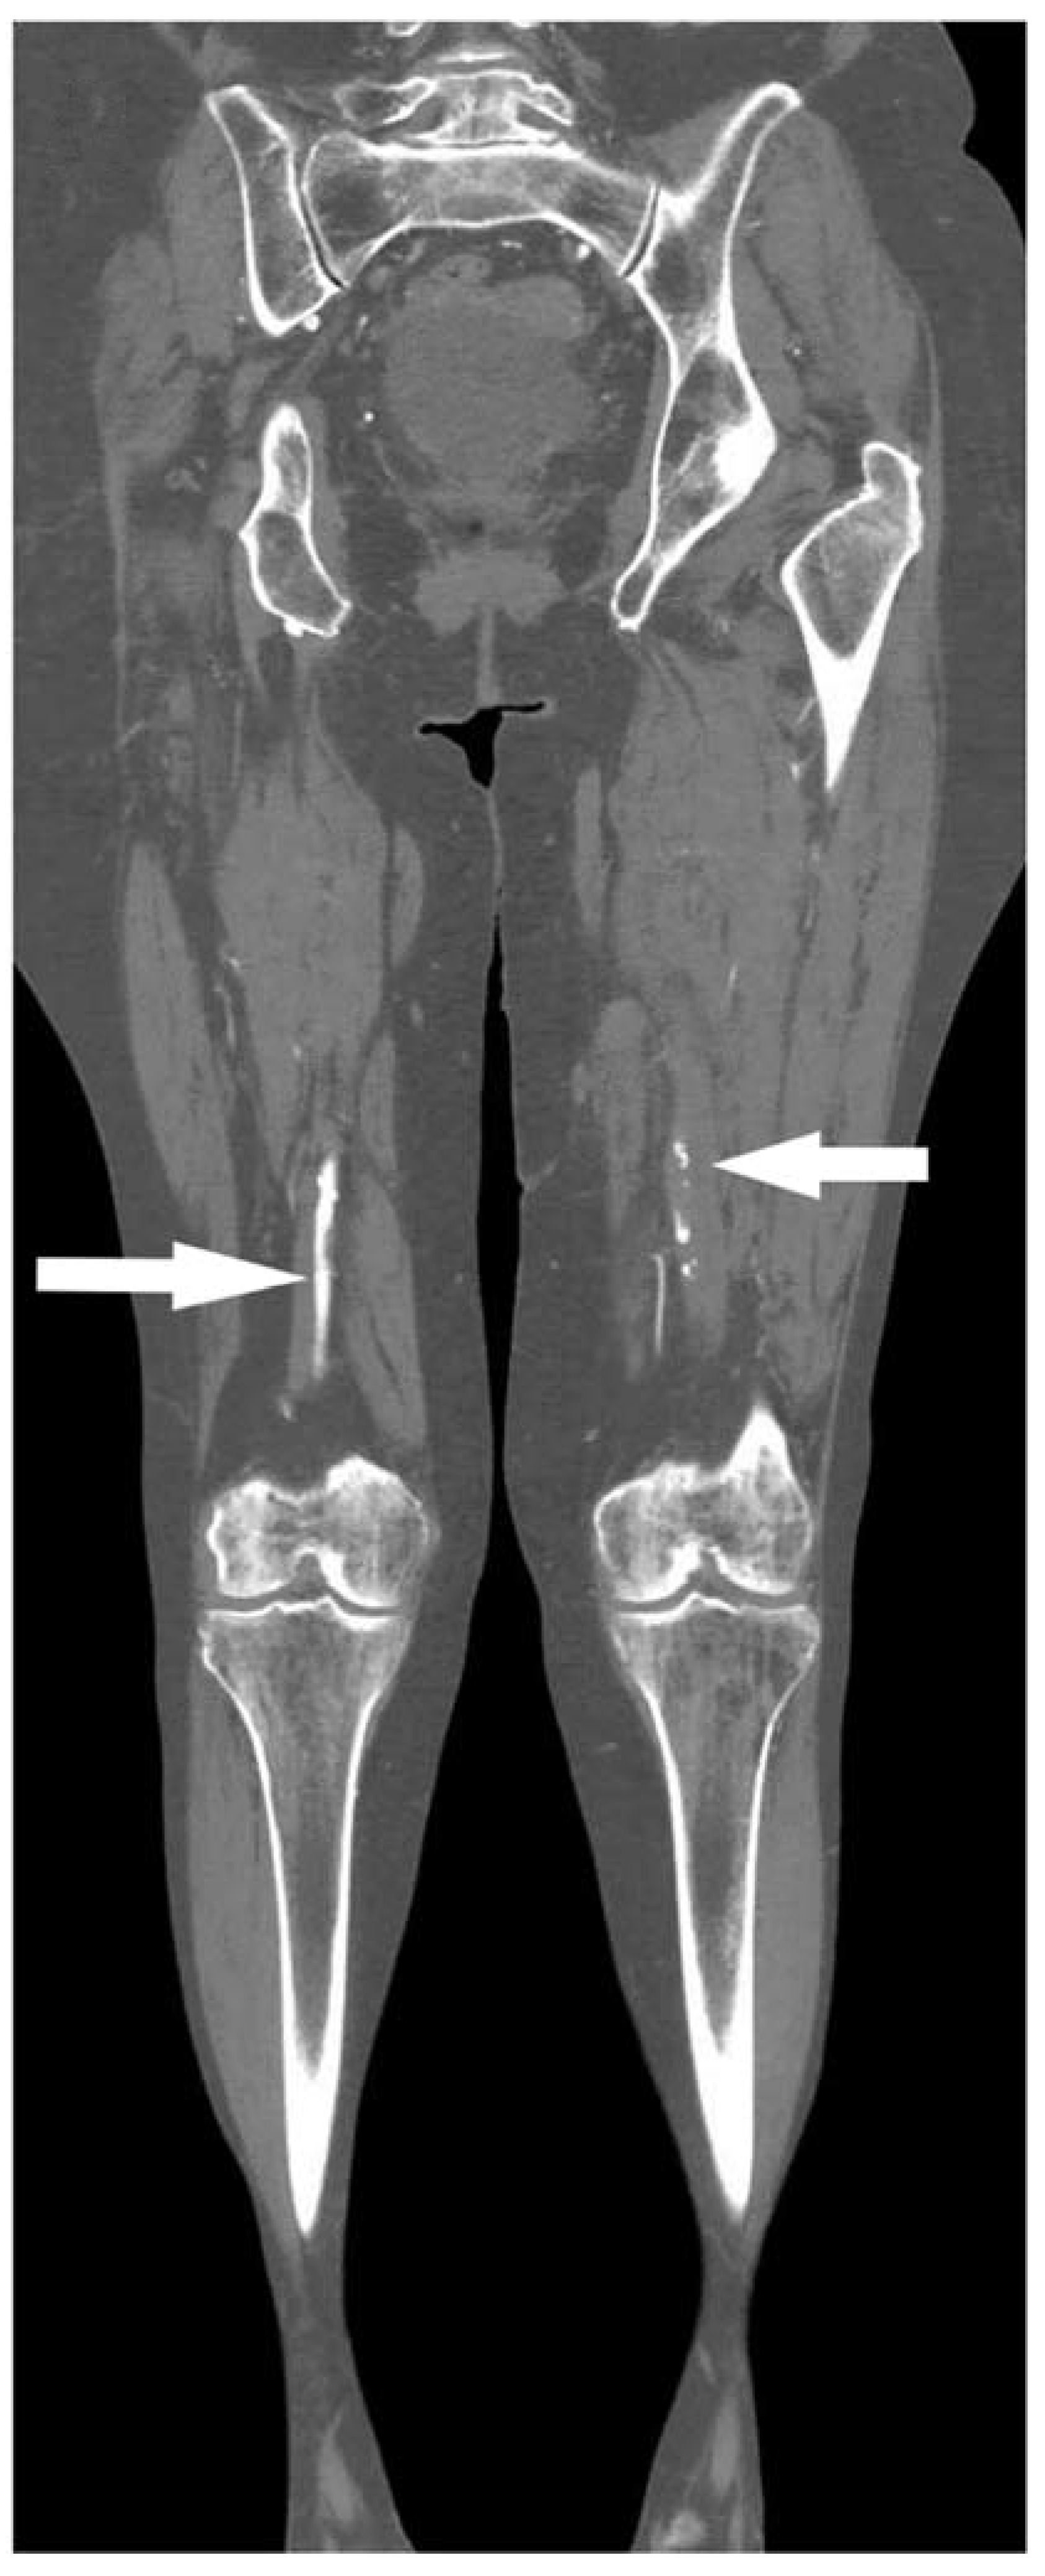

| Thrombus length, n (%) b | |||

| Short segment occlusions (<10 cm) | 36 (32.4) | 34 (30.6) | 2 (1.8) |

| Intermediate segment occlusions (10–20 cm) | 21 (18.9) | 13 (11.7) | 8 (7.2) |

| Long segment occlusions (>20 cm) | 54 (48.7) | 39 (35.1) | 15 (13.5) |